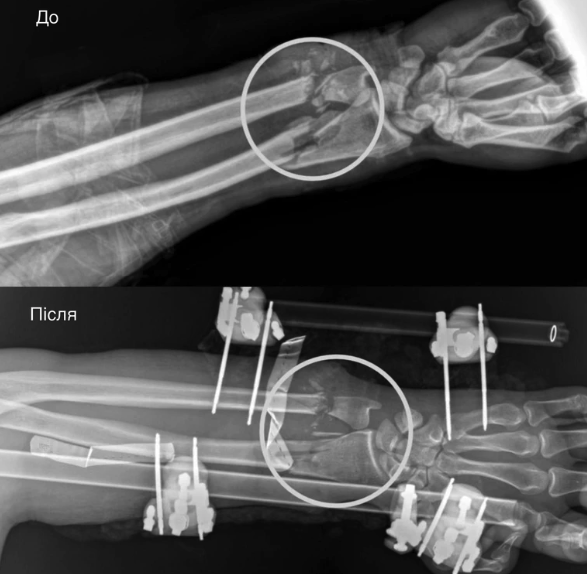

Травма була критичною: рука фактично трималася лише на шкірі. В чоловіка були повністю пересічені артерії, пошкоджені кістки, м'язи, сухожилля та нерви. За порятунок кінцівки взялася мультидисциплінарна команда медиків.

Спершу ортопеди-травматологи стабілізували переломи за допомогою апарата зовнішньої фіксації. Далі судинні хірурги відновили кровопостачання, зшивши пошкоджені судини – саме цей етап був вирішальним, адже без циркуляції крові тканини швидко змертвіли б.